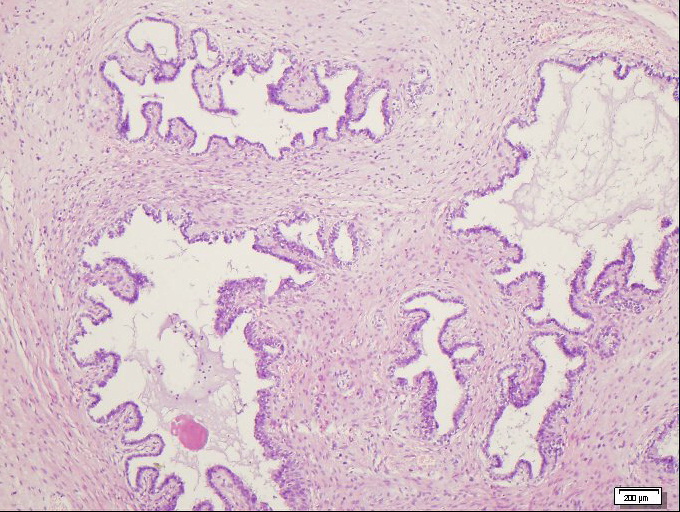

术后病理检查结果为畸胎瘤。